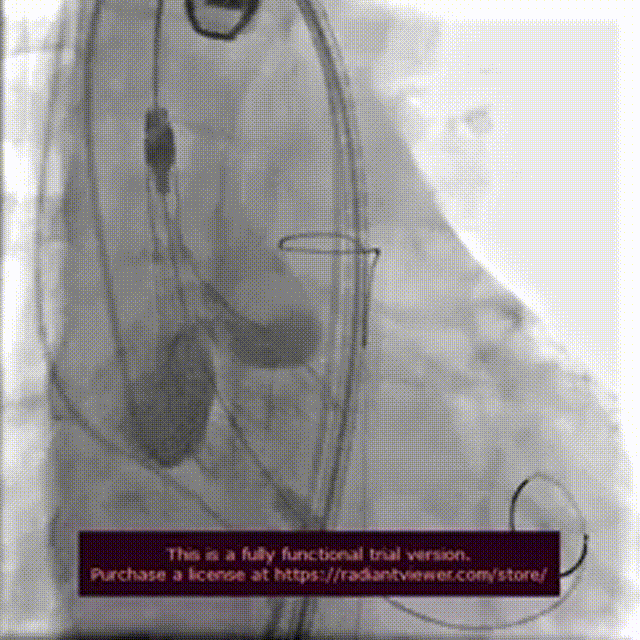

手术过程:

术前造影检查,主动脉瓣大量返流

圈套器辅助下,送入30mmVitaflow瓣膜

造影定位,可见无冠瓣叶较高

快速起搏条件下前期释放2/3瓣膜

造影显示瓣膜位置良好后完全释放

术后造影

数字减影模式检查下肢血管